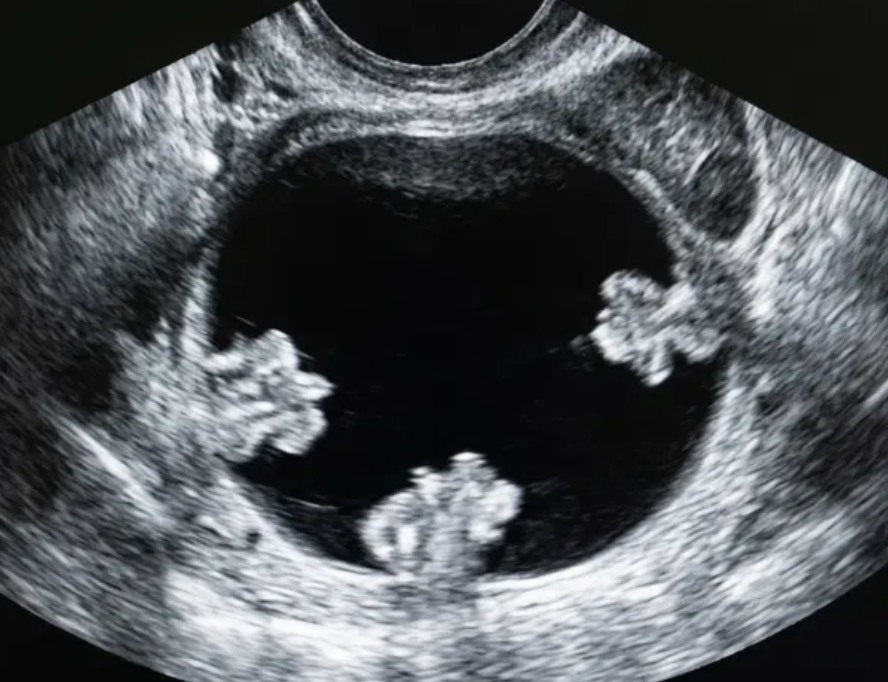

Risco: <10%Cisto unilocular ≥ 10 cm, cistos dermoides/endometriomas/hemorrágicos ≥ 10 cm, cisto unilocular com parede irregular < 3 mm, cisto multilocular < 10 cm com parede lisa, lesão sólida com superfície lisa.

Achados ultrassonográficos

O-RADS US 4 — Risco Intermediário

Risco: 10-<50%Cisto multilocular sem componente sólido ≥ 10 cm ou com IC = 4, cisto unilocular/multilocular com componente sólido, lesão sólida com superfície lisa e IC = 2–3.

Cisto multilocular, sem componente sólido

Cisto unilocular com componente sólido

Cisto multilocular com componente sólido

Lesão sólida